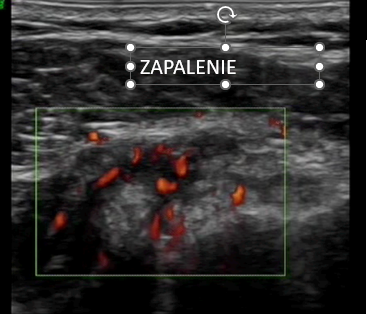

8. Zmiany zapalne i choroby układowe

W przebiegu chorób takich jak:

- reumatoidalne zapalenie stawów

- dna moczanowa

USG może ujawnić:

- wysięk

- przerost błony maziowej

- złogi patologiczne